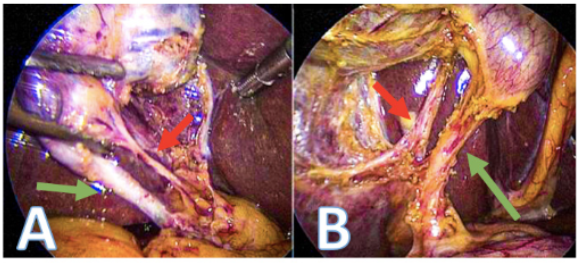

Establecer la identificación de la visión crítica de seguridad: La VCS puede ser comprobada usando una doble visión, anterior y posterior, de las estructuras (figura 6).

Deben observarse dos, y solo dos estructuras que ingresen a la VB, que representan el conducto y la arteria císticos, en una vista anterior y posterior9. Una vez establecida esta visión, recomendamos una pausa y una confirmación entre el cirujano y el ayudante quirúrgico, antes de cortar cualquier estructura (figura 4). En esta pausa, la identificación de la anatomía aberrante es crítica, una comprensión profunda y una apreciación de la anatomía aberrante es importante para minimizar el riesgo de una LVB. Una consideración común es asegurar que la arteria hepática derecha no se confunda con la arteria cística o la rama accesoria posterior en el área de la placa cística. En este punto se puede considerar el uso de CTO, en caso de ser necesario.